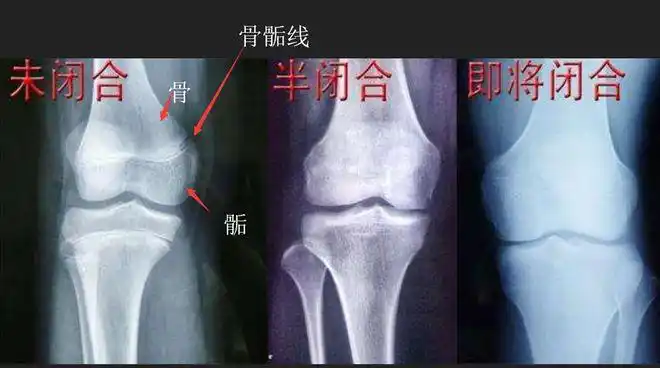

请您帮我看下我的骨骺线闭合了没有,还有长高的希望吗?

求看骨骺线 前三张是今天拍的后两张是去年三月拍的 我还能长几年?

骺板提早消失,骨不能长长.

大家帮我看看骨垢线有没有闭合,谢谢!